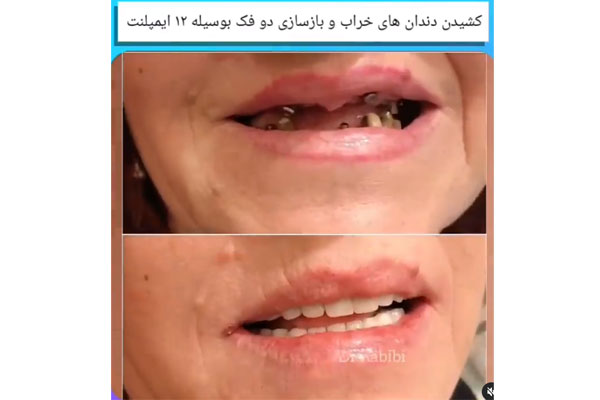

ایمپلنت دیجیتال روشی بسیاری جدی و نوین برای جایگزینی دندان و کاشت ایمپلنت است و مزیت های بسیاری نسبت به کاشت ایمپلنت معمولی دندان دارد. در این روش دندانپزشک به صورت کامل در کوتاه ترین زمان ممکن ایمپلنت دیجیتالی و پروتز دندان را با بالاترین کیفیت توسط داده های کامپیوتری که از اسکن دهان و فک شما گرفته می شود طراحی میکند و این طراحی باعث می شود تا محل دقیق کاشت دندان شما مشخص شود.

ایمپلنت دیجیتال دقت بسیار بالایی دارد و برای افرادی که تعداد ایمپلنت دندان بالایی دارند، به صورت بسیار آسان و دقیق عمل میکند و نتیجه ای فوق العاده طبیعی و شبیه به دندان های اصلی می دهد. این روش دارای ظرافت و زیبایی بوده و کمترین میزان درد را در میان سایر کاشت های ایمپلنت دیجیتال دارد. اگر شما نیز ساکن تهران هستید و به دنبال مرکز ایمپلنت دیجیتال در تهران هستید ادامه این مطلب را از دست ندهید.

همانطور که اشاره کردیم، معمولا برای پر کردن ناحیه بی دندانی یا جایگزین کردن دندان از دست رفته، به جز پروتزهای متحرک یا به وسیله بریج (روکش های متصل به هم) استفاده می شود و یا از کاشت دندان یا ایمپلنت استفاده می گردد. ایمپلنت به روش پانچ نوعی جراحی ساده کاشت دندان میباشد با کمترین درد و خونریزی انجام می شود.این روش برای افرادی کاربردی است که دارای بافت نرم در لثه و بافت محکم در استخوان داشته باشند. ایمپلنت دیجیتال دارای ظرافت و درصد خطایی پایین تری است و رضایت بیماران بیشتری دارد. در معرفی مراکز ایمپلنت دیجیتال در تهران، لیست کامل را برای شما قرار خواهیم داد. هم چنین برای مشاهده بهترین پزشکان برای ایمپلنت در شمال تهران می تواند به صفحه مربوطه مراجعه نمایید.

ایمپلنت یک روزهیک روش کاشت ایمپلنت است که به منظور جایگزین دندان های از دست رفته و شکسته مورد استفاده قرار میگیرد پایه های ایمپلنت شبیه ریشه دندان های طبیعی در استخوان فک عمل کرده و پایه بسیار مستحکمس برای سوار کردن تاج های دندانی که ظاهر شبیه دندان های طبیعی دارند بوجود می آورد.در روش های کاشت ایمپلنت سنتی دوره بهبود پس از کاشت پایه و پیش از نصب تاج دندان بسیار طولانی است در صورتی که فرایند ایمپلنت یک روزه روشی کاملا خاص و کاربردی است .

که با اسفاده از ان جای خالی دندان در یک روز توسط پایه ایمپلنت و تا دندانی پر می شود. البته در روش کاشت ایمپلنت فوری تاج دندان موقتی تا زمانی که تاج دندان اصلی برای نصب اماده شود روی پایه سوار میشود و زیبایی دندان های شمارا تکمیل می کند.